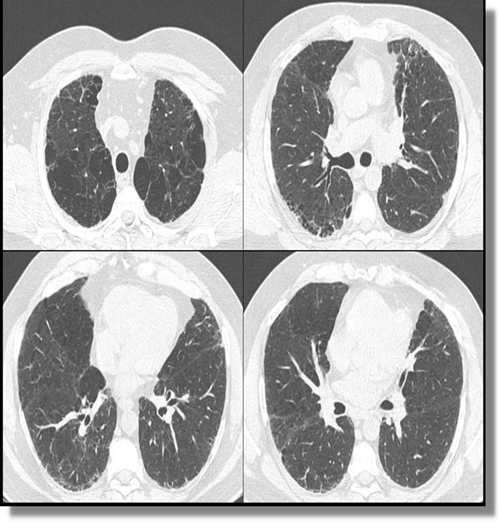

Se indica Tomografía de Tórax y Espirometría

Atento a estos estudios se decide realizar biopsia pulmonar por VATS.(sin complicaciones),pensando en posible intersticiopatía.

ENFISEMA y FPI